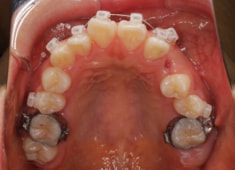

左上3番埋伏歯

治療法:フルパッシブブラケット:T21

治療開始時